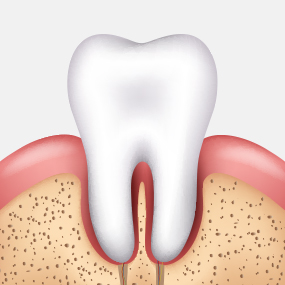

건강한 잇몸

치주낭 길이 3mm 이하

스케일링 치료